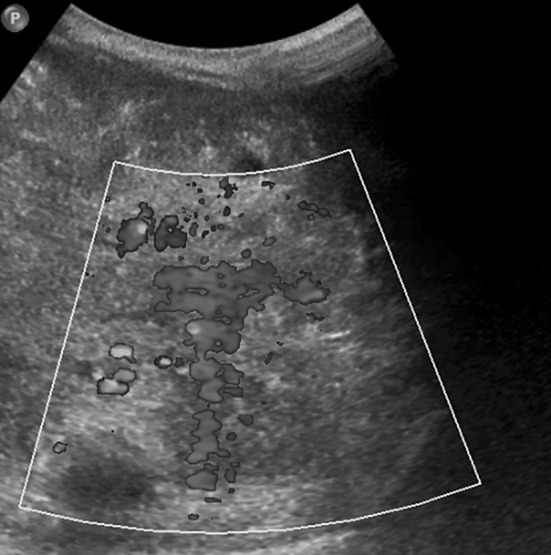

Three months old, developmentally normal female infant was evaluated for an incidentally noticed ill-defined, nontender, firm and immobile mass in the right paravertebral dorsolumbar region, with features of consumptive coagulopathy. Investigations revealed anaemia, thrombocytopenia and deranged PT/PTT. Ultrasound abdomen (Fig. 2) revealed an ill defined mixed echoeic mass lesion in the retroperitoneum, predominantly in the midline with extension to both paravertebral regions, with few calcific foci, encasing the vessels and infiltrating the pancreas. MRI abdomen (Fig. 1) confirmed the above findings, additionally revealing that the lesion was encasing the abdominal aorta, inferior vena cava and extending to the bilateral renal hila. The lesion was also extending superiorly from the level of the coeliac axis and inferiorly into the mesentery encasing the branches of the superior mesenteric vessels.

Fig. 2.

Doppler ultrasound abdomen showing increased vascularity of the tumor